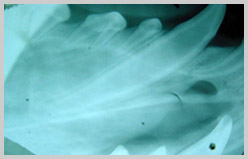

Bisecting angle technique for

maxillary cuspid (canine) in the cat.

Courtesy of Dr Verstraete